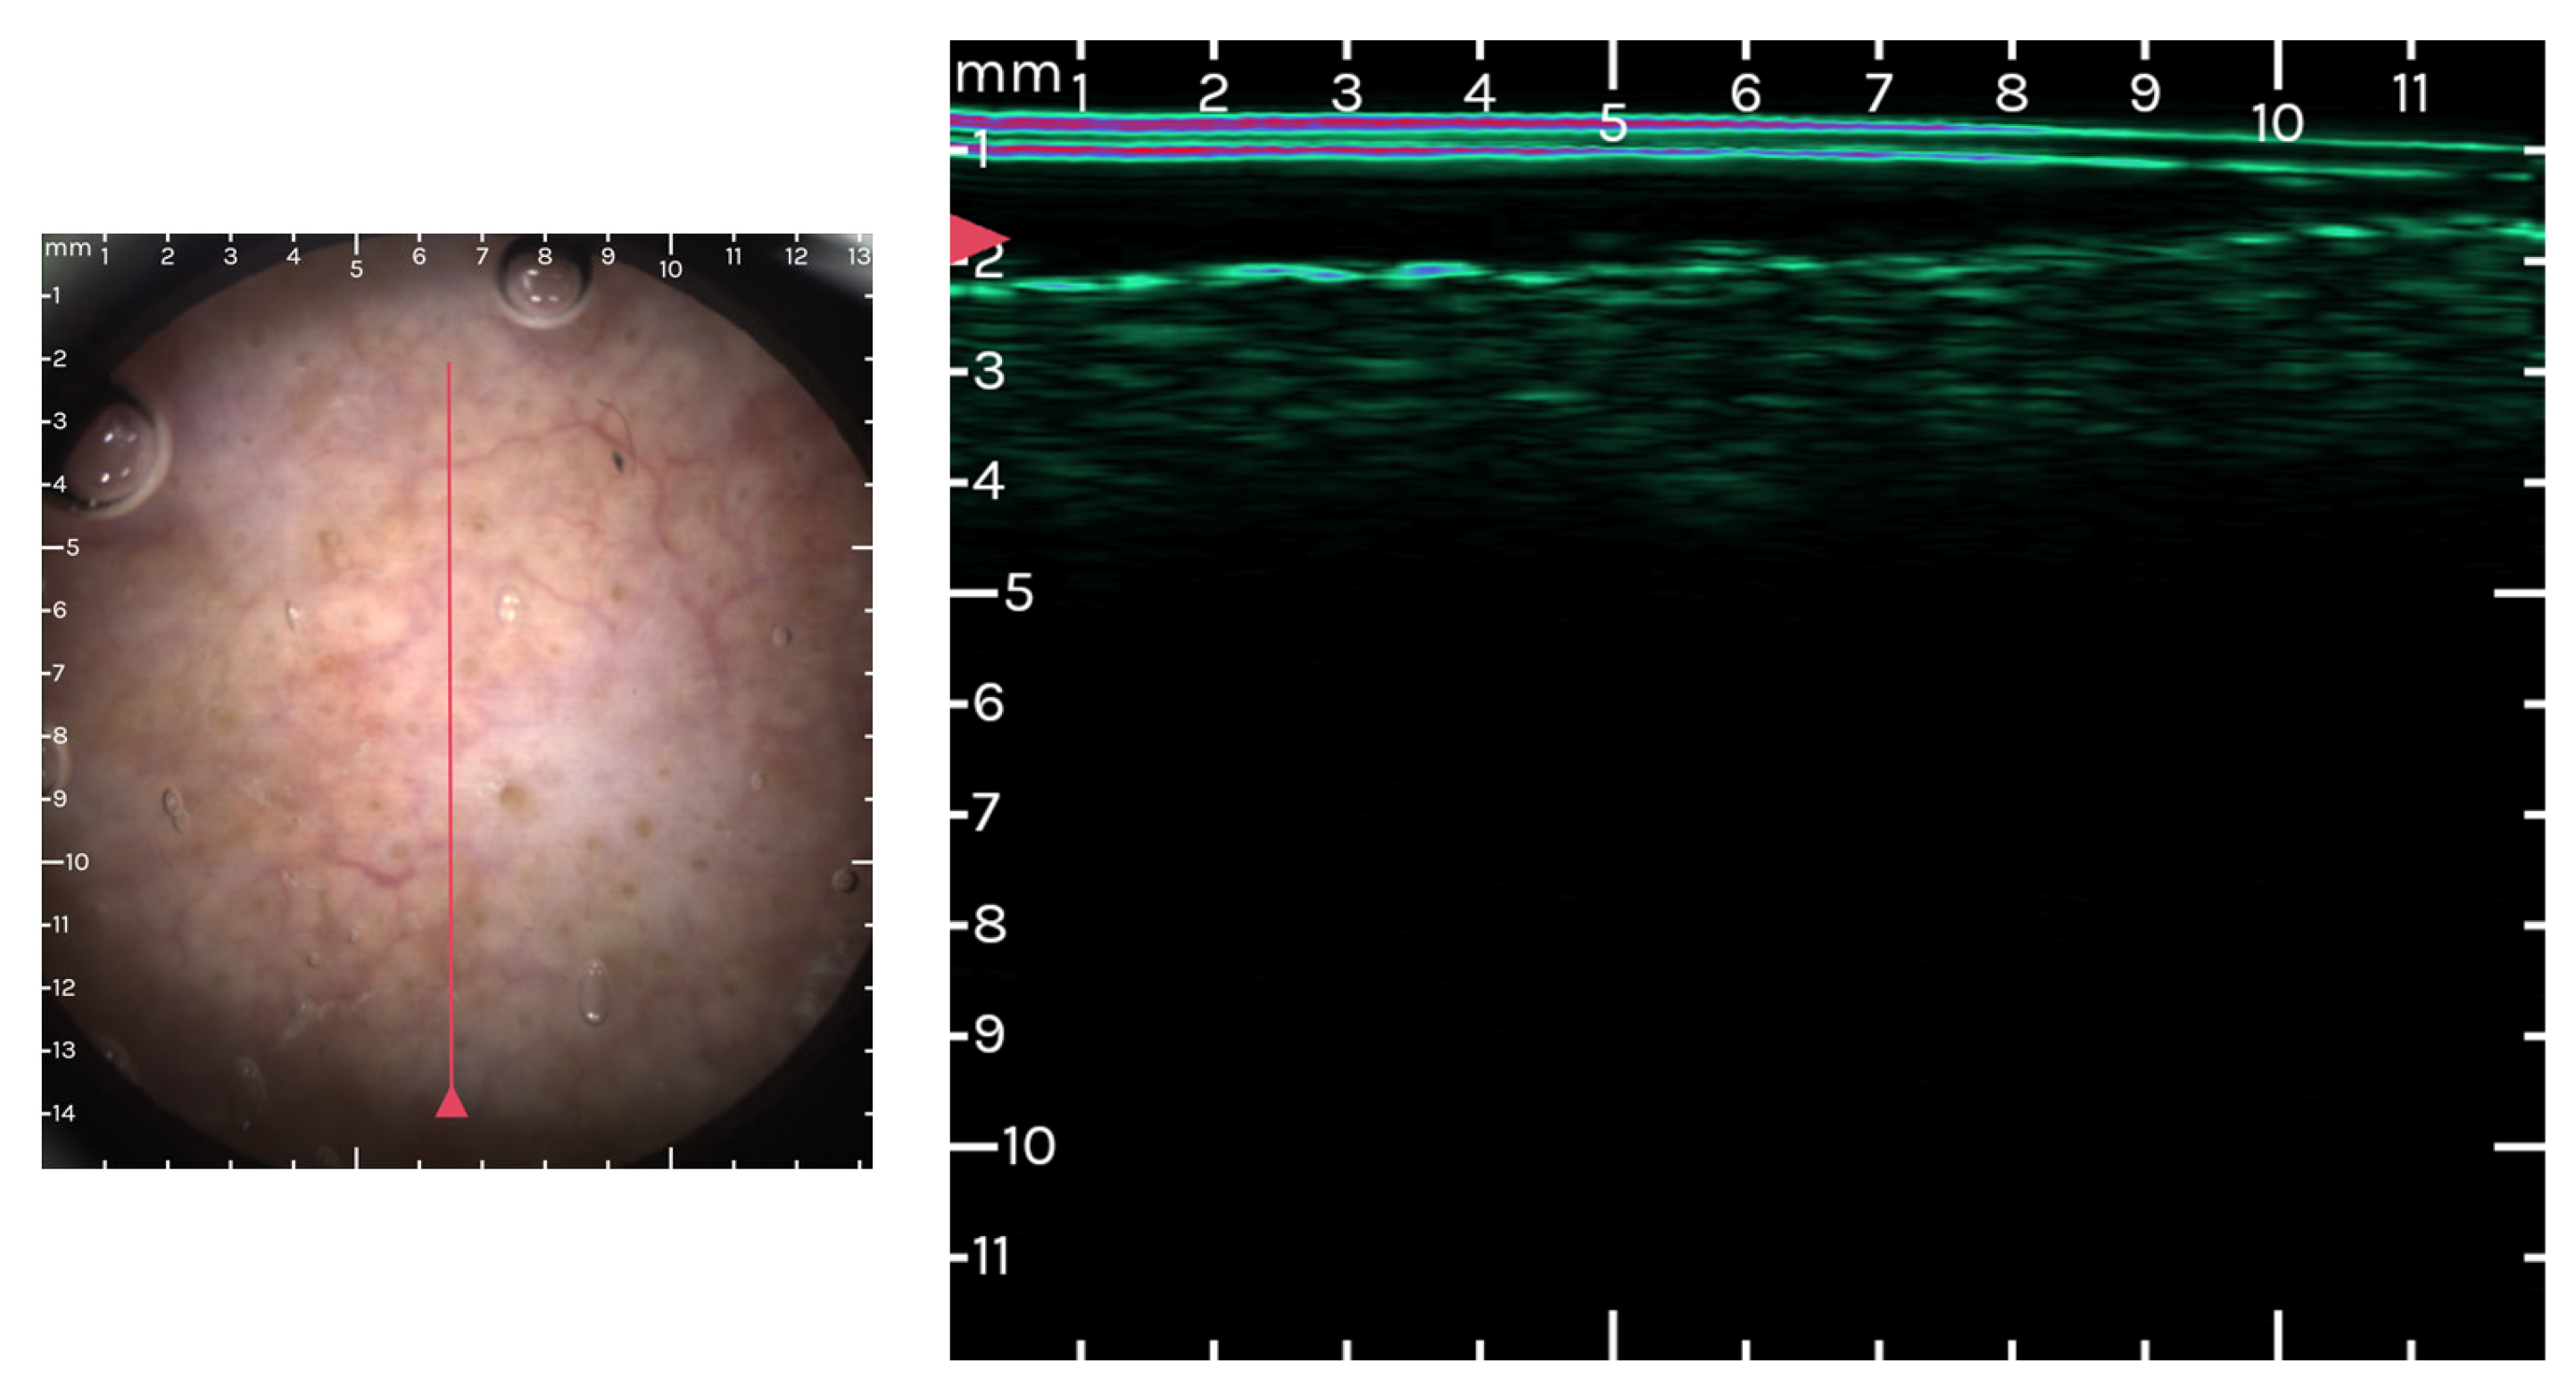

3.3. Optical Coherence Tomography (OCT) and AK

3.4. Ultrasound and High Frequency Ultrasound Imaging in AK